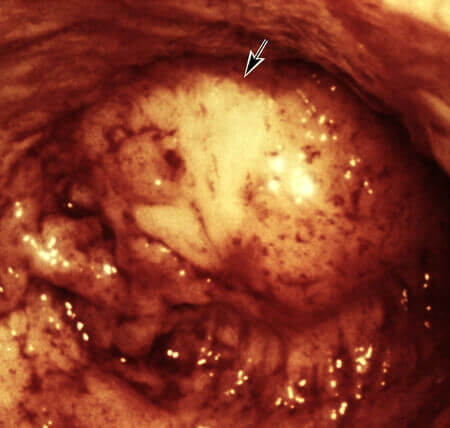

Además, pueden incluso destruir un cuerpo que parece joven y saludable. Yo diría que las muertes causadas por parásitos representan el 85 % de todas las muertes inesperadas o llamadas "súbitas". Mire estas fotos realizadas en nuestro laboratorio:

Hay parásitos dentro del corazón de una mujer de 45 años. La presencia de parásitos no se descubrió hasta después de su muerte:

Los parásitos en el corazón de la mujer de 45 años de edad que fueron encontrado después de su muerte: